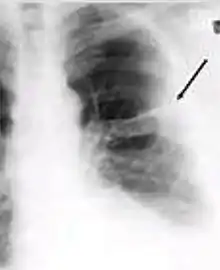

Chest x-ray of pleural thickening post-primary tuberculosis

1. Pleural thickening - Irregularity or abnormal prominence of the pleural margin, including apical capping (thickening of the pleura in the apical region). Pleural thickening can be calcified.